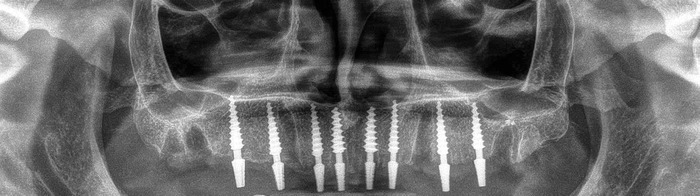

Вот снимки через 5 часов после операции:

На следующий день мне спреем обезболили верхние десны и Гоча снял финальный слепок челюсти. 5 числа вечером мне одели и за полтора часа подогнали верхнюю челюсть так, что когда я пришел на контрольный осмотр 6 числа - мне ничего подтачивать не пришлось. Гоча - мастер не меньший, чем Георгий и Хатуна.